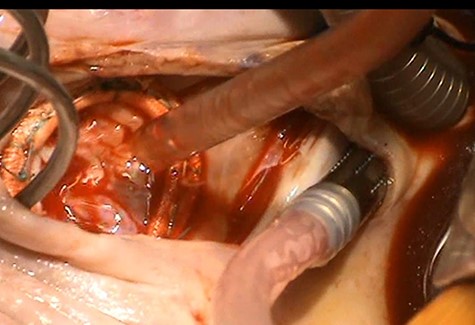

Intra-operatively there was an infected and destroyed anterior leaflet of the tricuspid valve with posterior leaflet prolapse causing severe tricuspid regurgitation (Fig. 1). There was evidence of raised pulmonary artery pressures and right ventricular dysfunction. A detailed assessment of the remnants of the native tricuspid valve was performed on the operating table to devise a complex reconstructive strategy.

Anterior leaflet destroyed by vegetation and posterior leaflet prolapse.